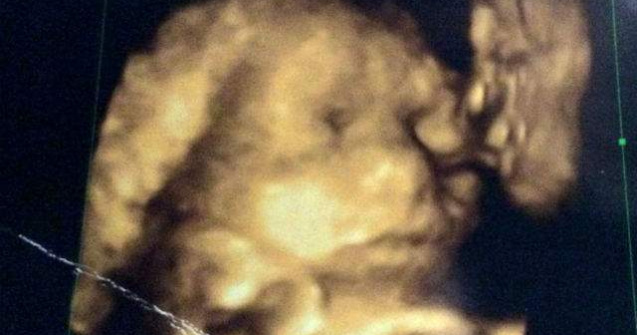

Ecografie 4d